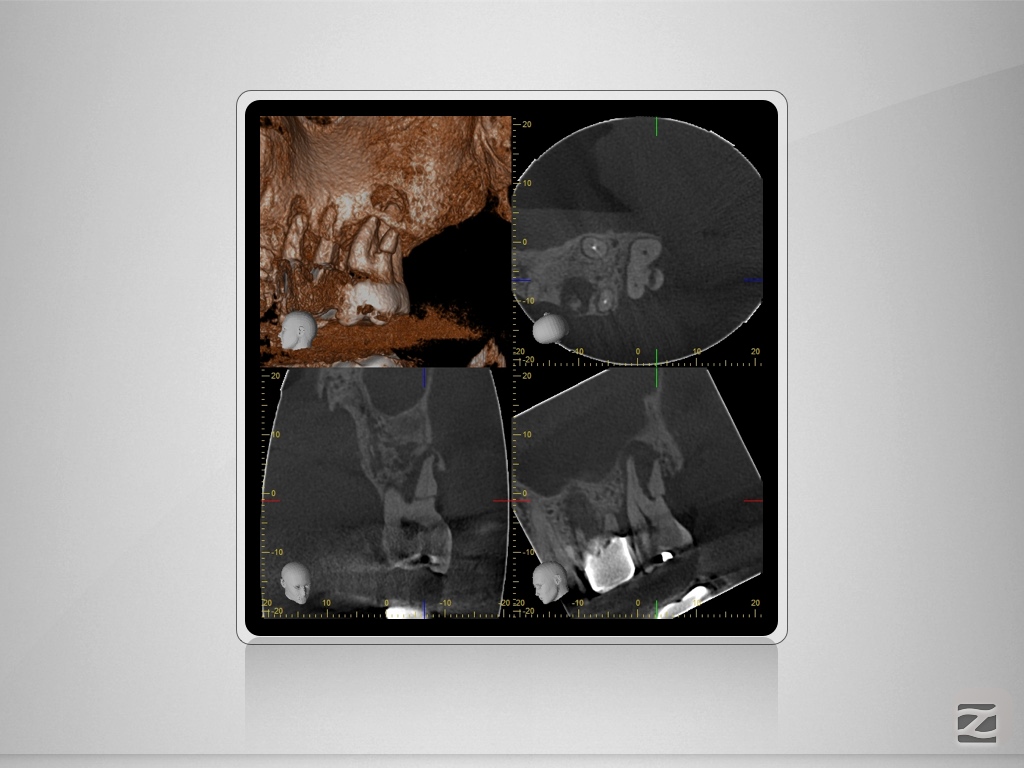

27D.006

Vorher/Nachher – Die Auflösung